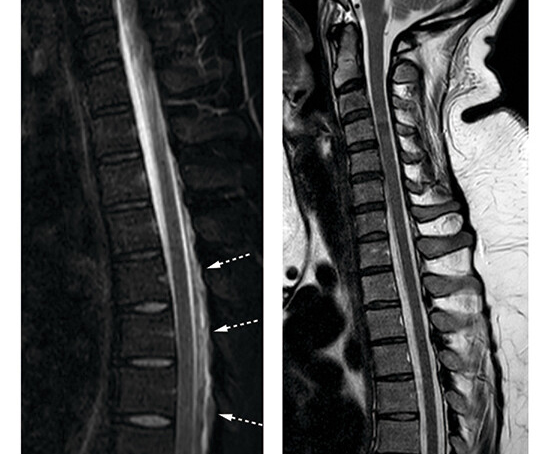

Bildene viser nevroaksen hos en tidligere frisk kvinne i 30-årene. Sagittalt T1-vektet bilde av caput (bilde A) viser forstørret hypofyse (hvit pil) samt at hjernestammen og lillehjernetonsillene har sunket ned mot foramen magnum (stiplet svart pil). Sagittalt T2-vektet, fettsupprimert bilde av cervikotorakalcolumna (bilde B) viser en epidural væskebrem i nivå Th4–Th9 (hvit pil). Det ble også påvist (ikke vist her) fortykkede meninger (FLAIR-serie) og en subdural væskebrem med blodprodukter langs tentoriet (susceptibilitetsvektet serie).

MR-funnene og sykehistorien vekket sterk mistanke om spontan intrakranial hypotensjon (SIH). Pasienten ble i forkant av torakal epidural blodlapp, hvor 20 mL autologt venøst blod ble injisert i nivå Th7/Th8, behandlet med flatt sengeleie og peroral fenazon-koffein og acetazolamid. Prosedyren ble etterfulgt av 24 timers sengeleie med 30 graders senket hodeende (Trendelenburgs posisjon). Hun opplevde god effekt av behandlingen og kunne skrives ut til hjemmet etter tre dager. To måneder senere var hun i betydelig bedring og medikamentfri. Tre måneder etter blodlapp så man normaliserte intrakraniale forhold og kun en beskjeden mengde restvæske i epiduralrommet spinalt (figur C og D).

Spontan intrakranial hypotensjon er trolig underdiagnostisert og kjennetegnes av ortostatisk hodepine, som ved postpunksjonshodepine, og eventuelt andre nevrologiske symptomer som gjerne fluktuerer ved stillingsendring og/eller bevegelse. Ved mistanke om denne lidelsen bør pasienten henvises til nevrolog for vurdering av andre potensielt alvorlige årsaker til sekundær postural hodepine, som for eksempel cerebral sinusvenetrombose eller subaraknoidalblødning. Ledsagende symptomer som kvalme med oppkast, nakkesmerter og -stivhet sees hos omtrent halvparten av pasientene (1). Typiske MR-funn er diffus meningeal fortykkelse og kontrastoppladning, venøs blodopphopning og kaudal ektopi av hjernen, men også forstørret hypofyse som hos vår pasient. Radiologisk utredning muliggjør lokalisering av lekkasje- og intervensjonsstedet og kan avdekke komplikasjoner som subdural hematomutvikling.